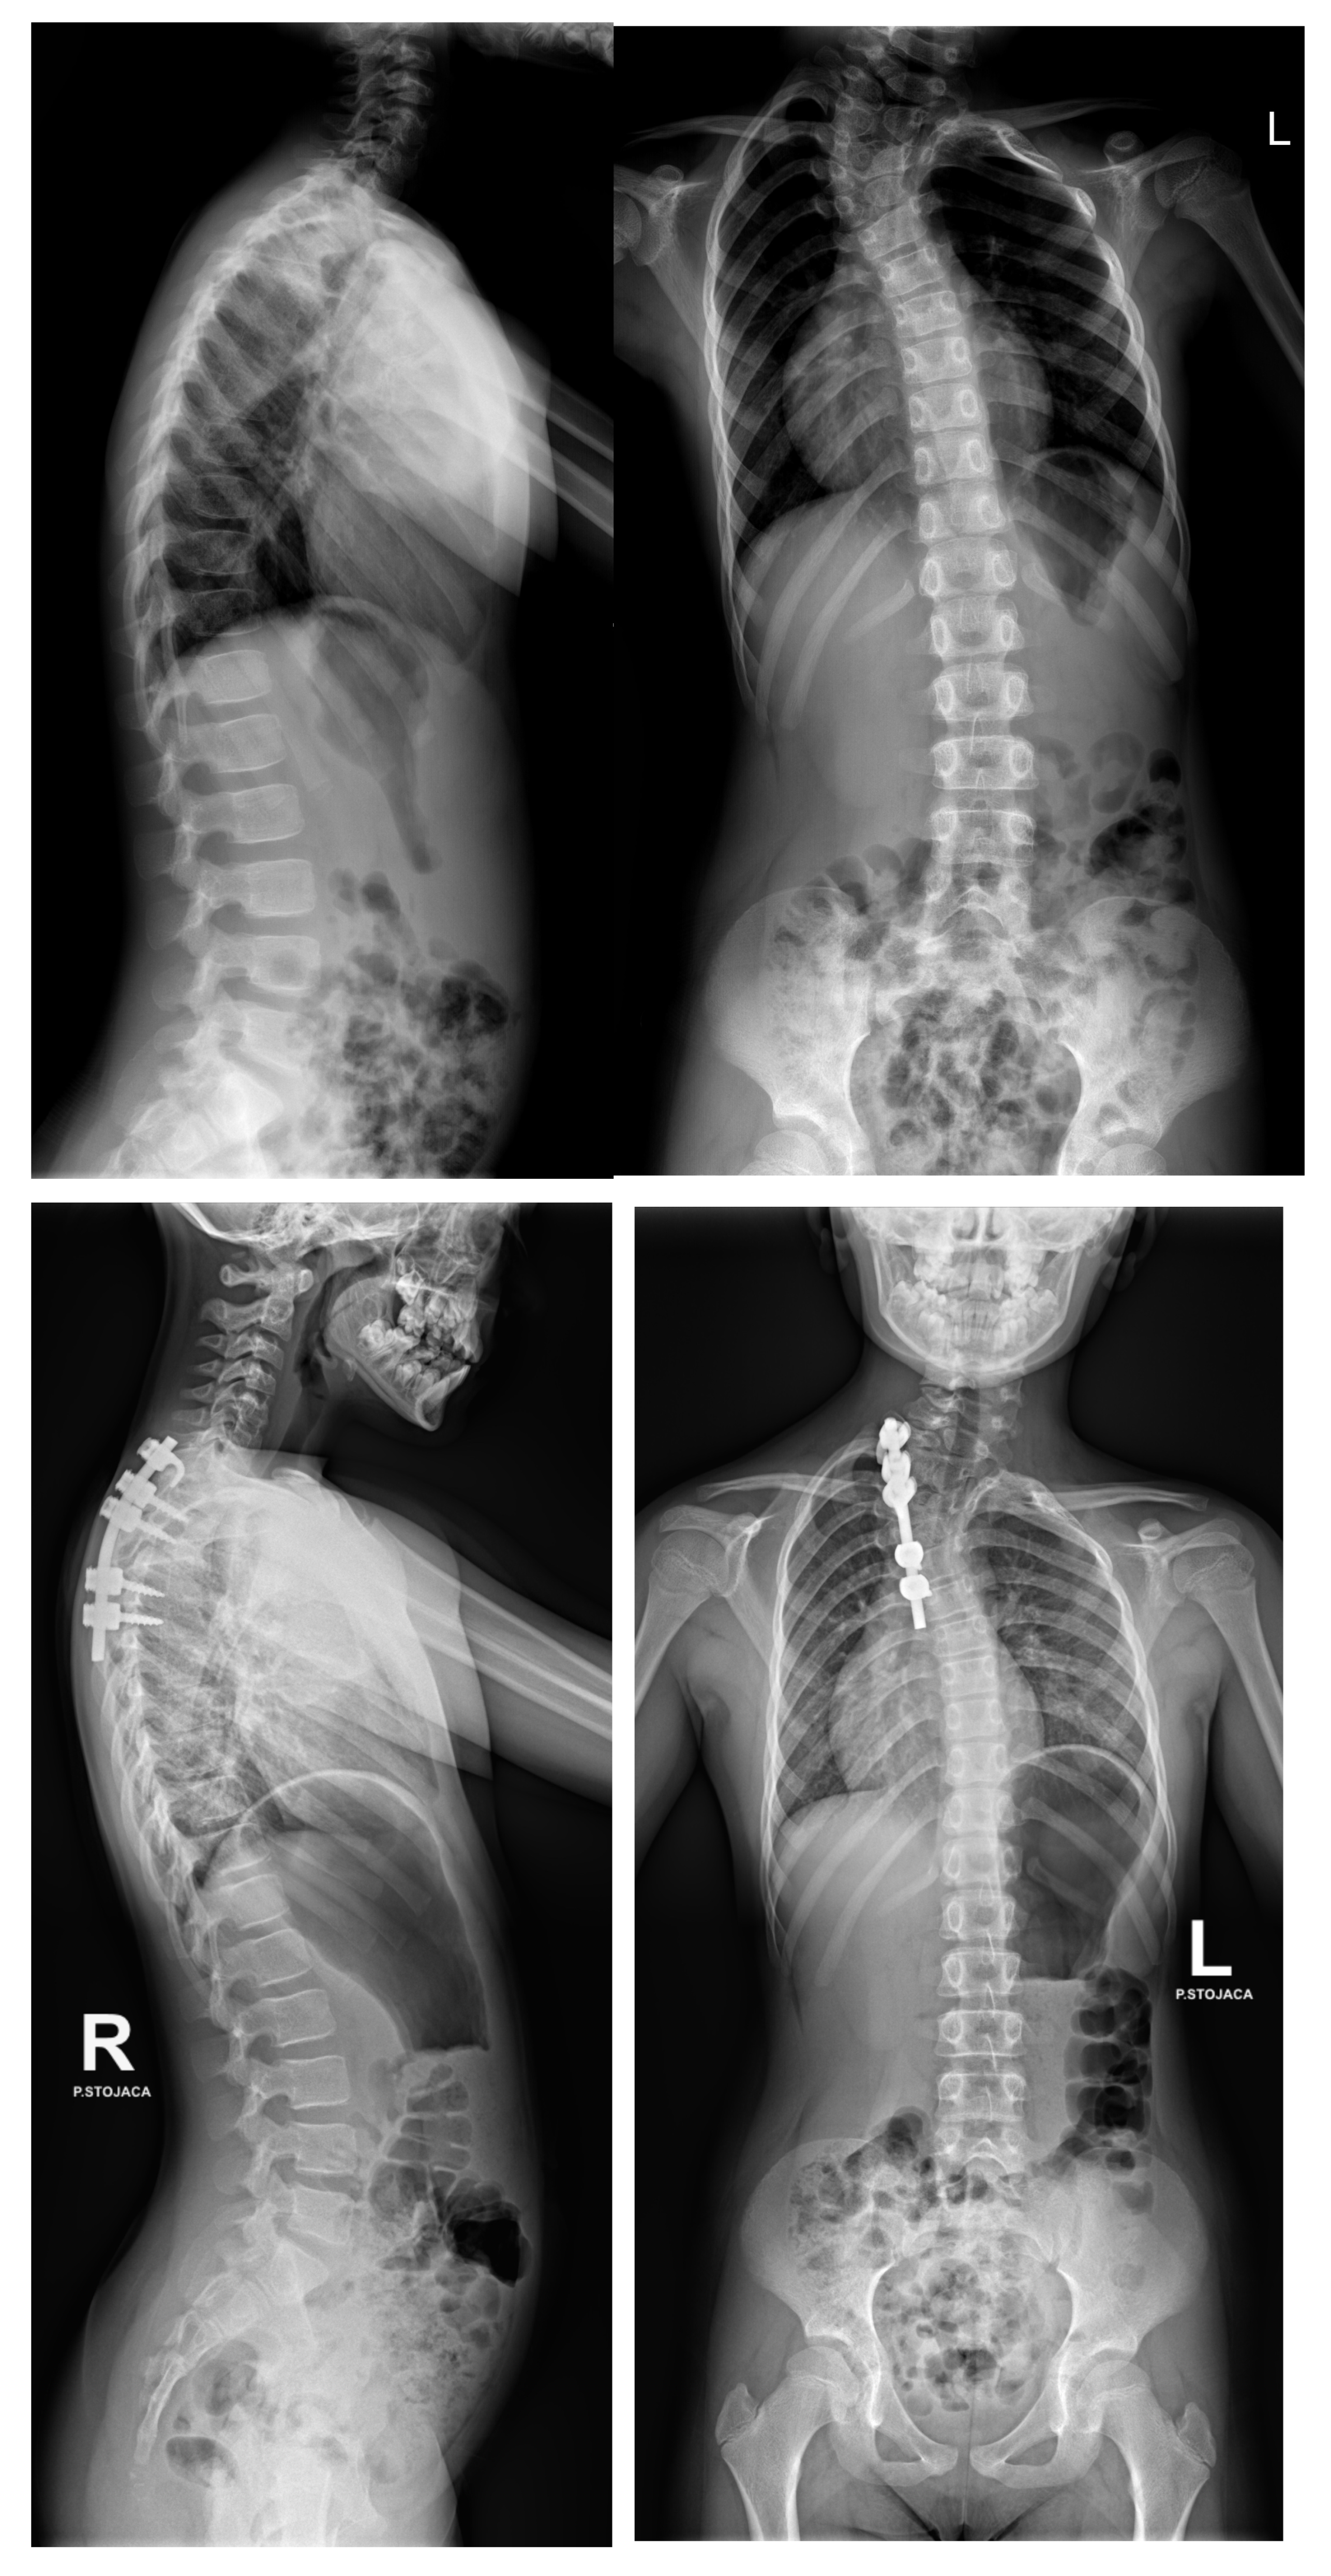

6.1. Radiographic Evaluation

6.2. Advanced Imaging Modalities

7.3. Surgical Techniques

7.3.4. Growing Rod Systems

7.3.6. Growth Guidance Systems—Shilla